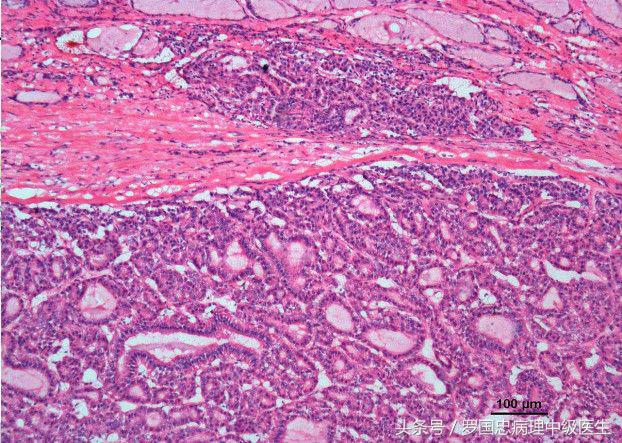

甲状腺癌是头颈部比较常见的恶性肿瘤,占全身恶性肿瘤的 1% -2%,女性多见,发病率为男性的2—3倍。甲状腺癌的病理类型较多,最常见的是乳头状癌和滤泡性癌。

甲状腺癌的预后:甲状腺癌病理类型很多,最常见的是乳头状癌和滤泡性癌。恶性度最高的是未分化癌,最低的是微小癌。甲状腺癌的预后非常好,个别恶性度高的除外,低度恶性的甲状腺癌可生存10年以上,有的其至肺部转移后还能带病生存5年左右,但高度恶性的甲状腺癌会在短期内死亡。一般甲状腺癌10年生存率可达到90%,笔者曾经遇到一例甲状腺癌,到现在已经有23年了依然健在。